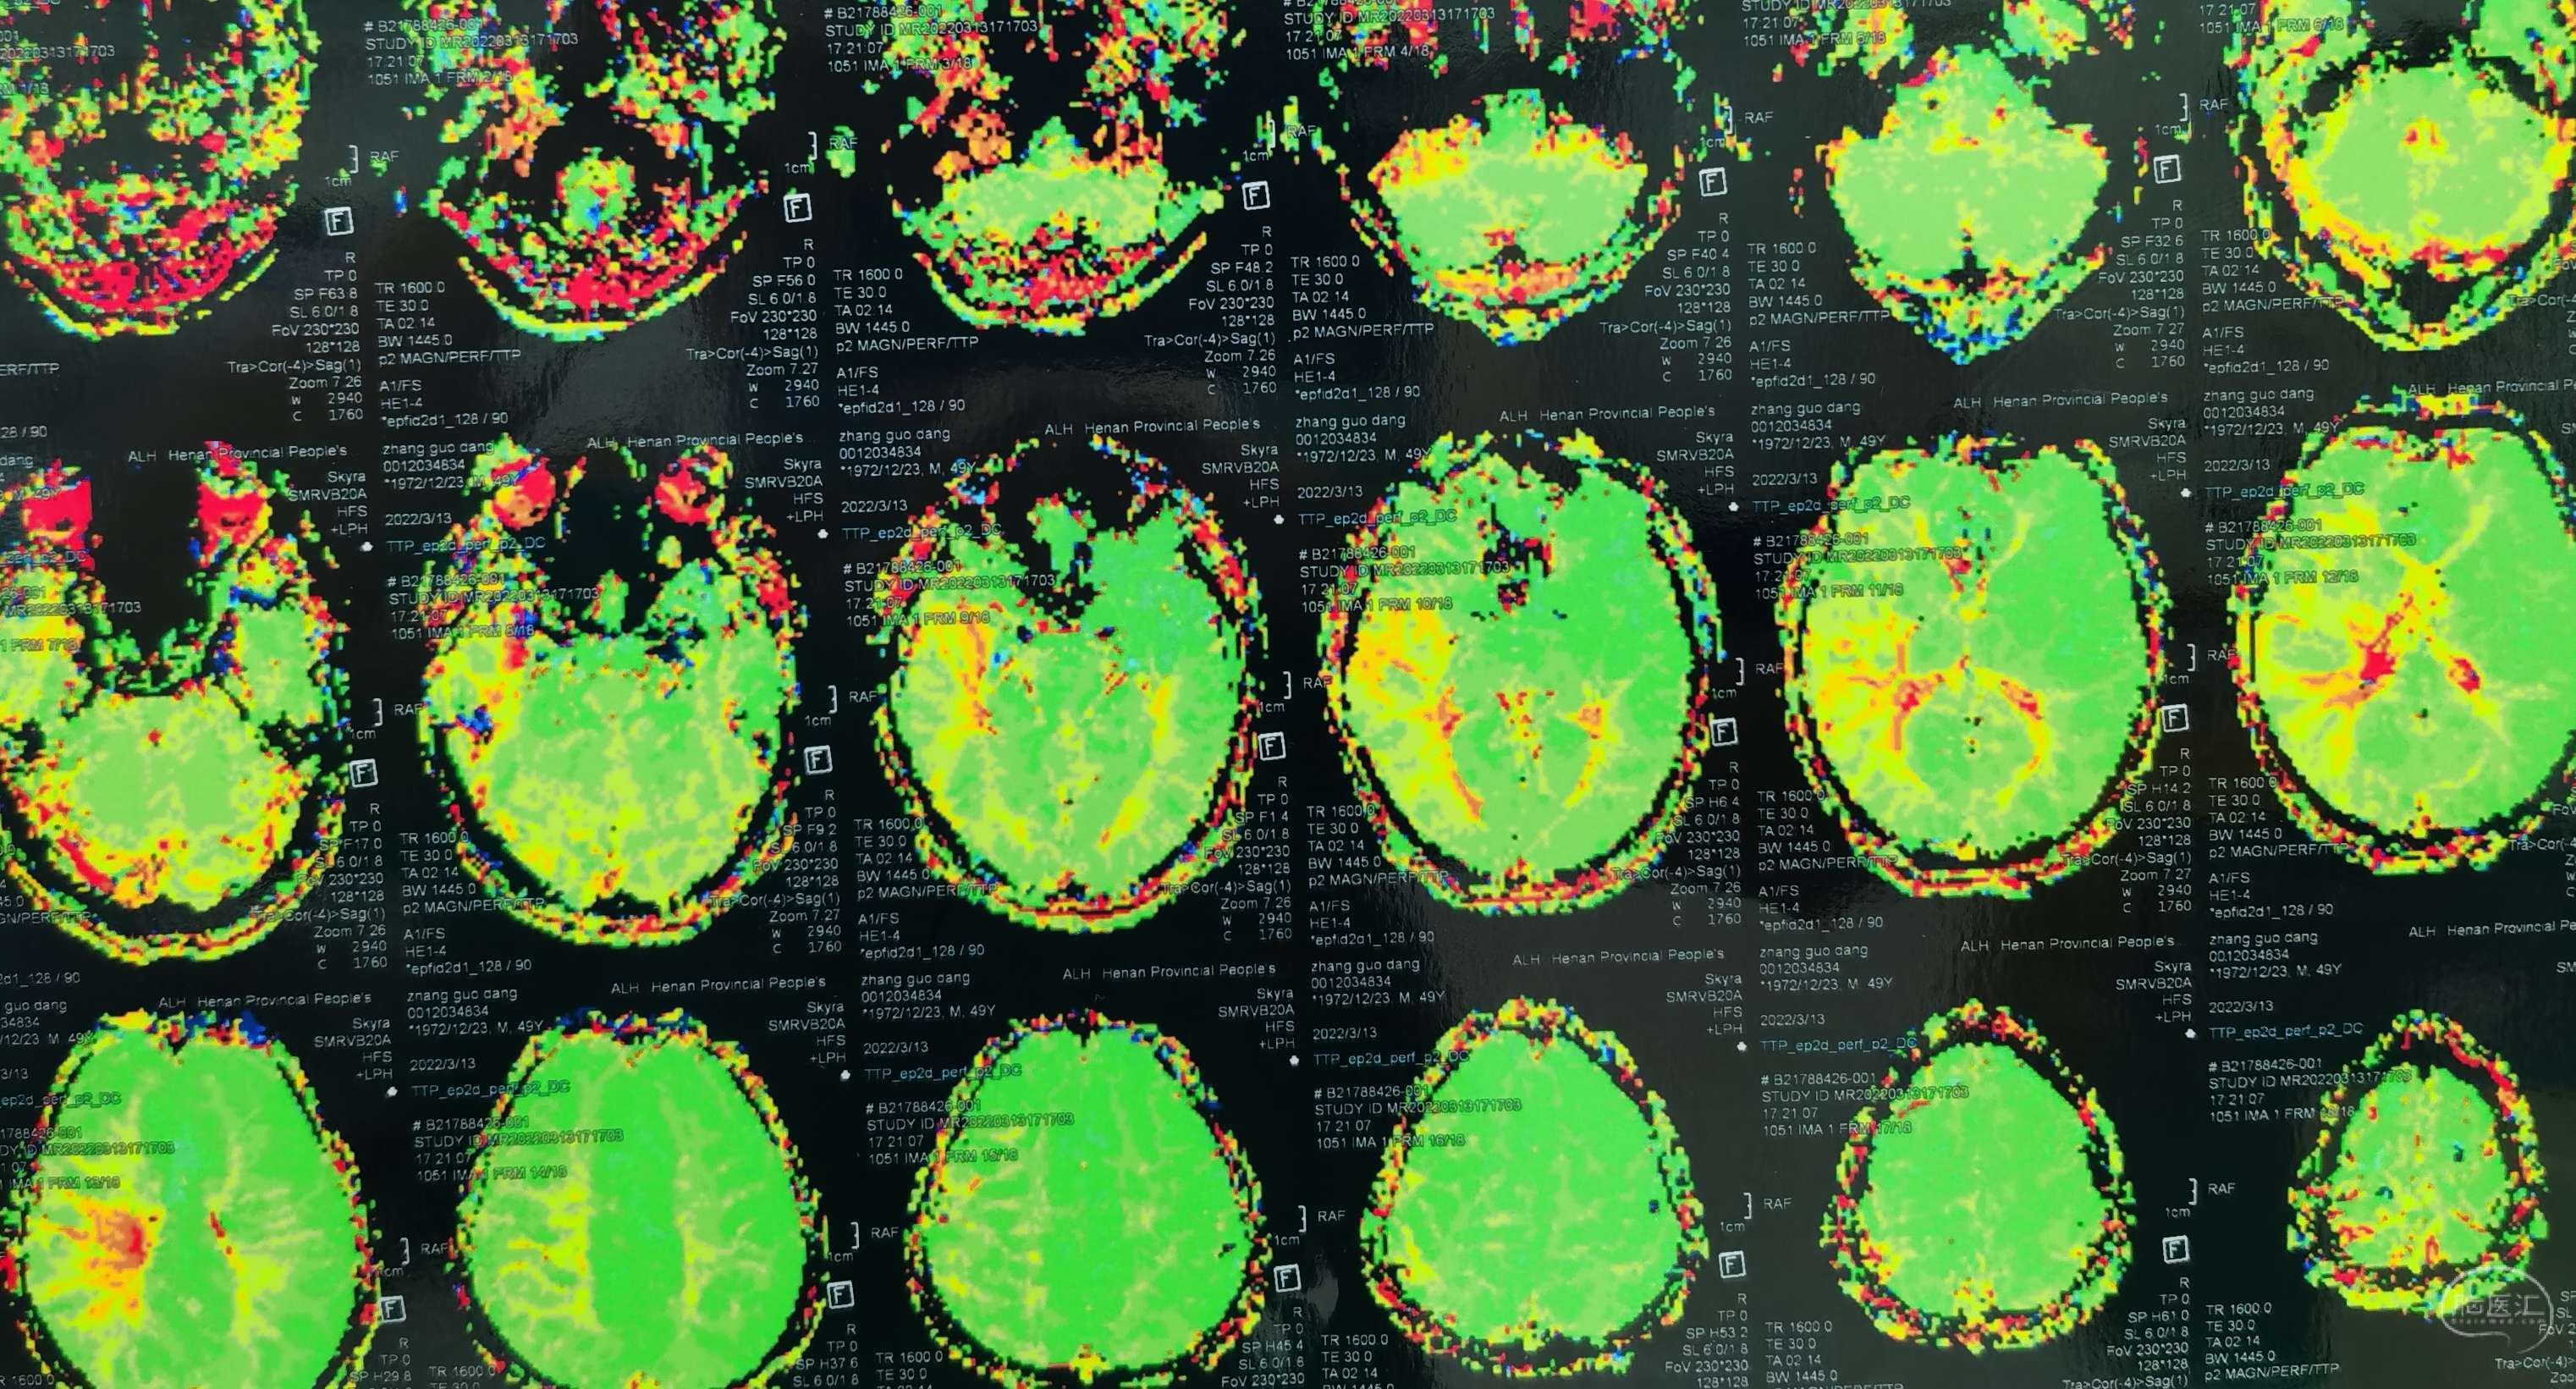

脑灌注提示:左侧大脑半球低灌注缺血。

脑灌注提示:右侧大脑半球低灌注缺血。

脑灌注提示:双侧大脑半球低灌注缺血。

脑灌注提示:双侧大脑半球低灌注缺血。

脑灌注提示:双侧大脑半球低灌注缺血。